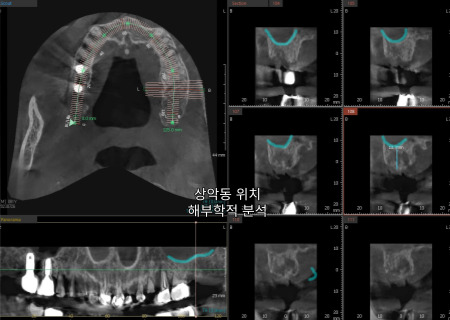

3D CT와 구강 스캔을 통해

사진처럼 3차원의

해부학적 구조를

관찰하는 모습입니다.

특히 위턱의 경우

입천장 부근에 있는

얇은 상악동 막이 존재해

다치지 않도록

심는 위치와 뼈상태를

정밀하게 살펴야 합니다.